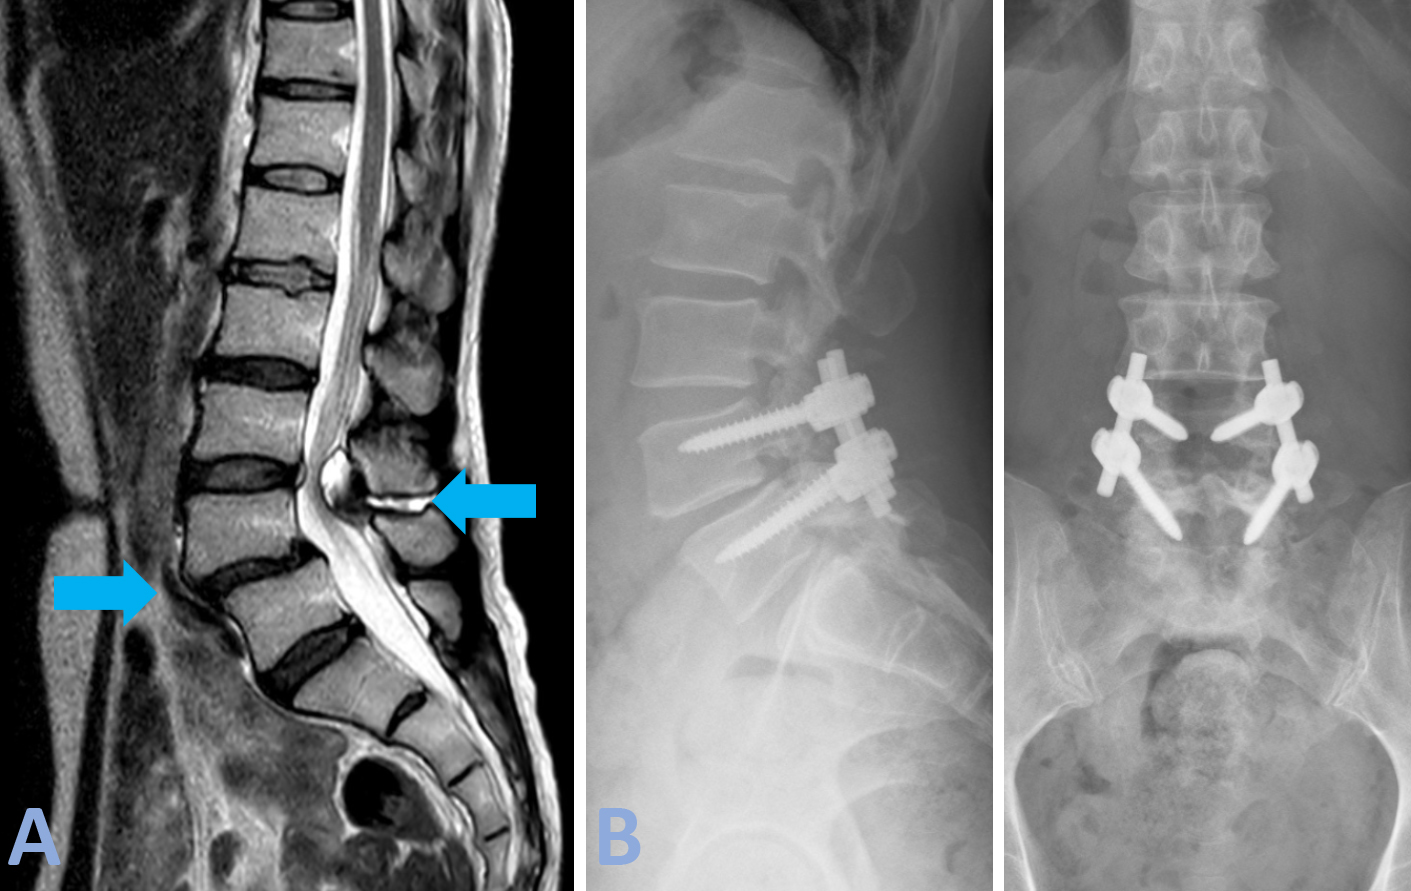

Patologia malformativa spinale Caso di paziente con tethered cord (midollo fissato) (midollo spinale fissato da un cordone fibroso a livello dell’osso sacro) associato ad un lipoma intradurale (tumore benigno di tessuto adiposo) a livello delle ultime radici spinali che presiedono al controllo degli sfinteri (freccia azzurra, Figura A).

È una condizione in cui il midollo spinale rimane ancorato verso il basso da un cordone fibroso (filum terminale) che lo stira verso il basso e ne causa sofferenza. In condizioni di normalità il midollo spinale termina a livello della prima vertebra lombare (cono midollare), nel caso presentato il midollo termina a livello della quinta vertebra lombare, perché stirato verso il basso. La paziente si presentava in ospedale per incapacità ad urinare (ritenzione urinaria) e perdita di feci (incontinenza). Veniva sottoposta ad intervento di disancoraggio midollare (sezione del cordone fibroso) e decompressione delle radici nervose mediante asportazione sub-totale del lipoma. L’intervento veniva eseguito sotto monitoraggio neurofisiologico per preservare la funzione dei nervi. La RM post-operatoria (Figura B) dimostra gli esiti dell’intervento con riduzione significativa del lipoma e detensione dei nevi e del midollo spinale (freccia rossa, Figura B). Nel post-operatorio si è assistito ad un miglioramento della funzione sfinterica della paziente.